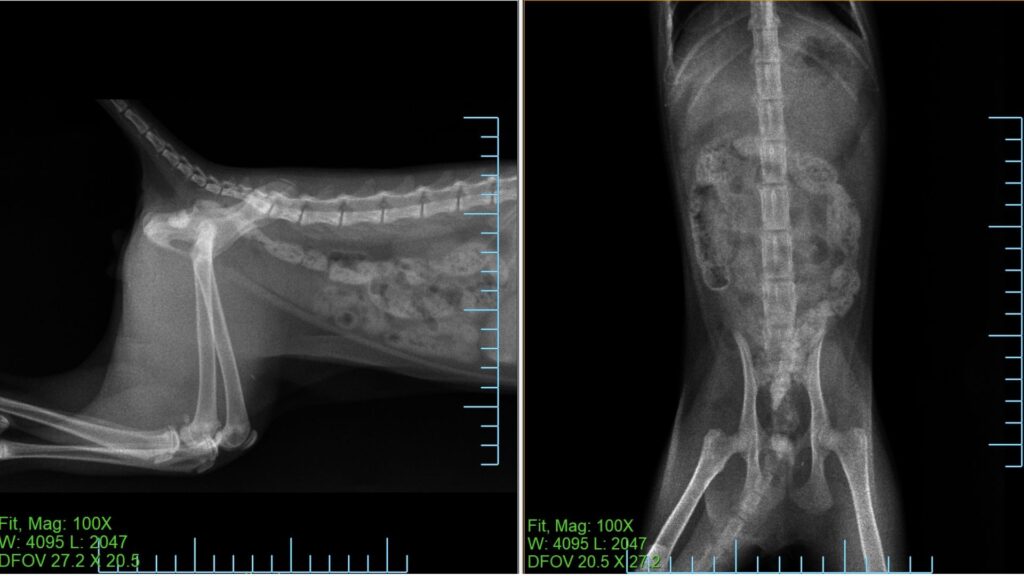

翌日(3月18日)の経過

翌日の再診では

• 元気あり

• 食欲あり

と体調に大きな変化はありませんでした。

前日は食事を半量与えていましたが、特に問題なく完食していました。

排便は軟便〜水様便でしたが、これは造影剤の影響と考えられました。

レントゲンでは造影剤が大腸まで到達していることが確認されました。

また便の中に

シリコンの紐状の異物

紙の破片

が排出されていることが確認されました。